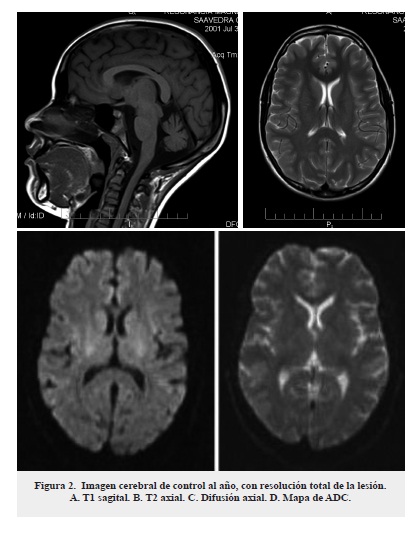

Paciente femenina de 11 años, quien consultó al servicio de urgencias por un cuadro de 3 días de evolución, inició con cefalea pulsátil frontal que empeoró progresivamente y posteriormente se acompañó de disartria, dificultad en la marcha con aumento del polígono de sustentación, fiebre cuantificada y somnolencia. No presentaba antecedentes médicos de importancia. Al examen físico de ingreso a urgencias se encontró un puntaje en la escala Glasgow de 10/15 (ocular 3, verbal 2, motor 5) con pobre seguimiento de instrucciones, escasa movilización espontánea de miembros superiores, todos los reflejos normales y sin signos meníngeos. Se consideró inicialmente como primera posibilidad diagnostica encefalitis y se iniciaron estudios, incluyendo una RMN cerebral simple y con contraste que mostró una lesión única en esplenio de cuerpo calloso hipointensa en T1 e hiperintensa en T2 y FLAIR, que restringe a la difusión en mapa de ADC, sin realce con el medio de contraste (figura 1). Se tomó estudio de líquido cefalorraquídeo (LCR) que mostró pleocitosis (184 células x mm3) linfocitaria (60 %), hiperproteinorraquia (125 mg/dL), lactato ligeramente elevado (3 mmol/L), con el resto de parámetros dentro de los rangos normales. El cultivo bacteriano y la reacción en cadena de la polimerasa (PCR) para Herpes I y II fueron negativos. Se completaron estudios con búsqueda de causas autoinmunes para lo cual se solicitaron: anticitoplasma de neutrófilo, complemento (C3 y C4), complemento CH50, anticardiolipinas IGG e IGM, anticuerpos anti ADN de doble cadena, Anti Ro y Anti Smith que estuvieron dentro de rangos normales. Se amplió estudio imagenológico con RMN de columna simple y contrastada, la cual no presentó lesiones.

En estudios imagenológicos de esta entidad se aprecian lesiones hipointensas en T1, hiperintensas en T2 y que restringen en difusión en mapa de ADC, las cuales involucran en todos los casos el esplenio del cuerpo calloso. Se ha subclasificado la entidad en MERS tipo1 y tipo 2 según la extensión de la lesión, en el primer caso la lesión está circunscrita al esplenio del cuerpo calloso, mientras que, en el segundo puede extenderse a lo largo de todo el cuerpo calloso y a la sustancia blanca extracallosal, principalmente frontoparietal. De estos dos patrones el primero es de mejor pronóstico1,2.